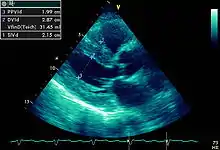

Hipertrofia ventricular esquerda

Hipertrofia ventricular esquerda é o espessamento da parede do ventrículo esquerdo. Apesar de encontrarmos no electrocardiograma sinais eléctricos de hipertrofia o seu estudo é feito pormenorizadamente em ecocardiografia.[1]

FIGURA 10

Heart left ventricular hypertrophy sa